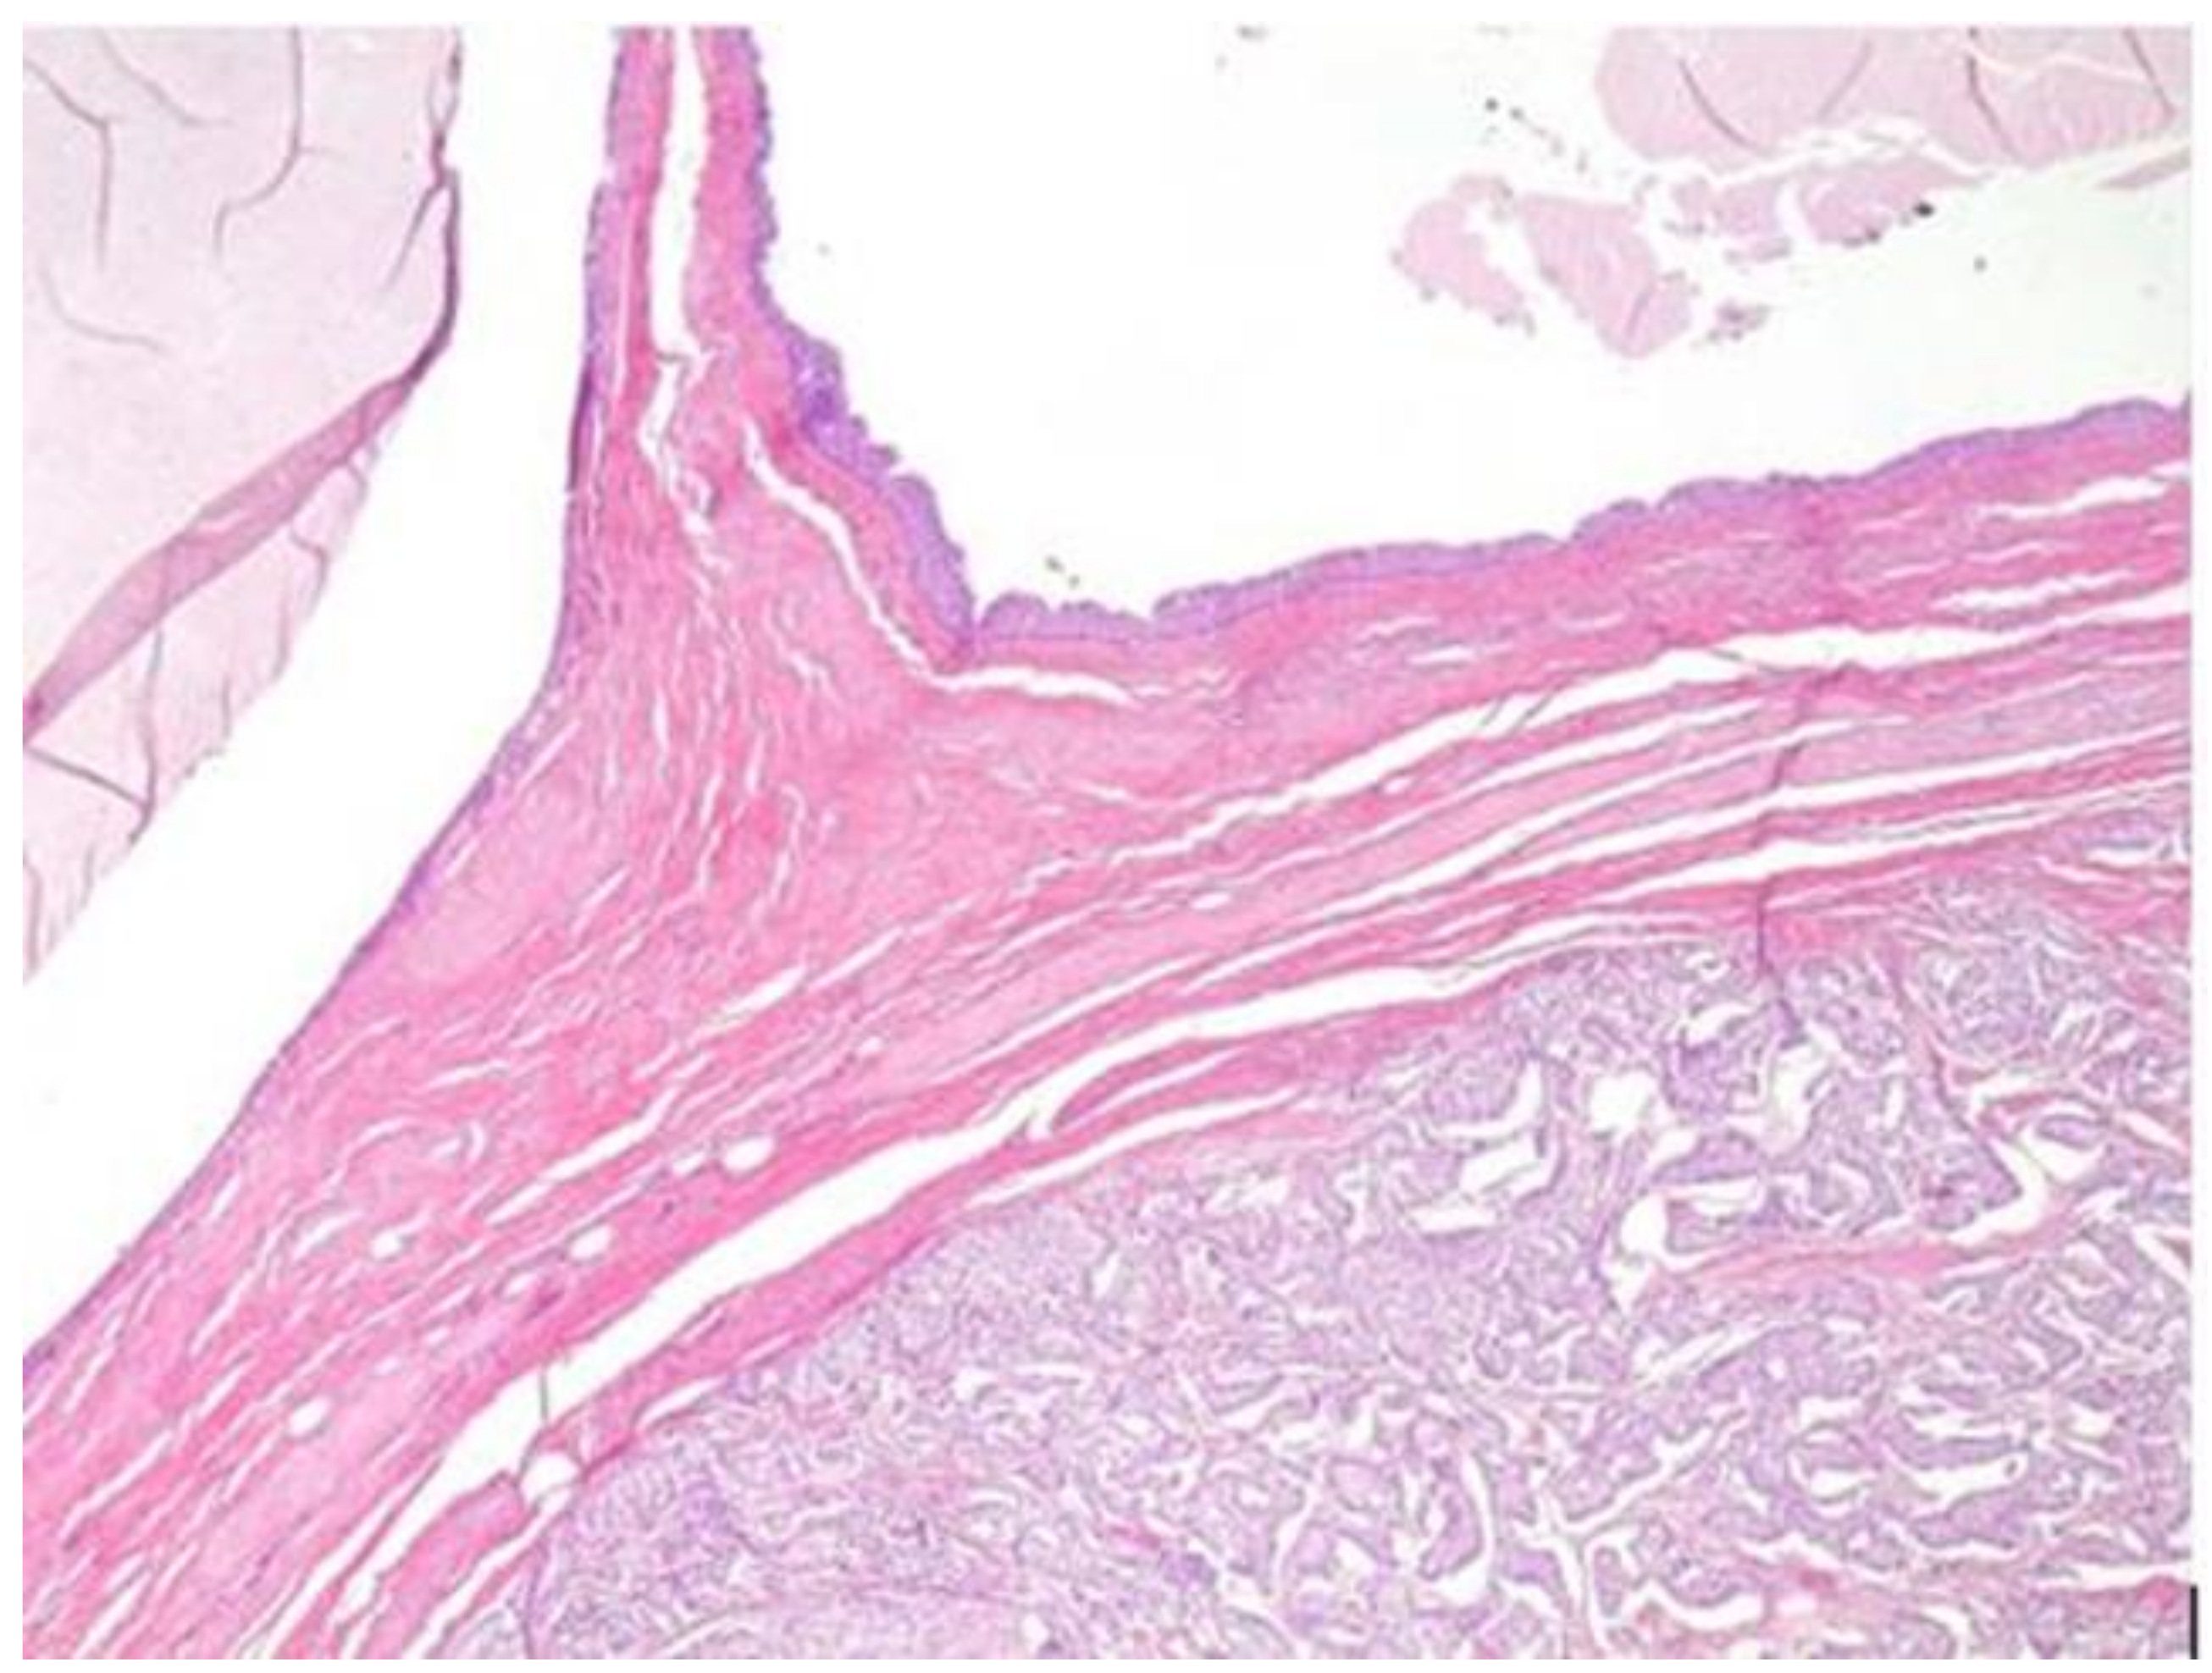

2.2. Pathology